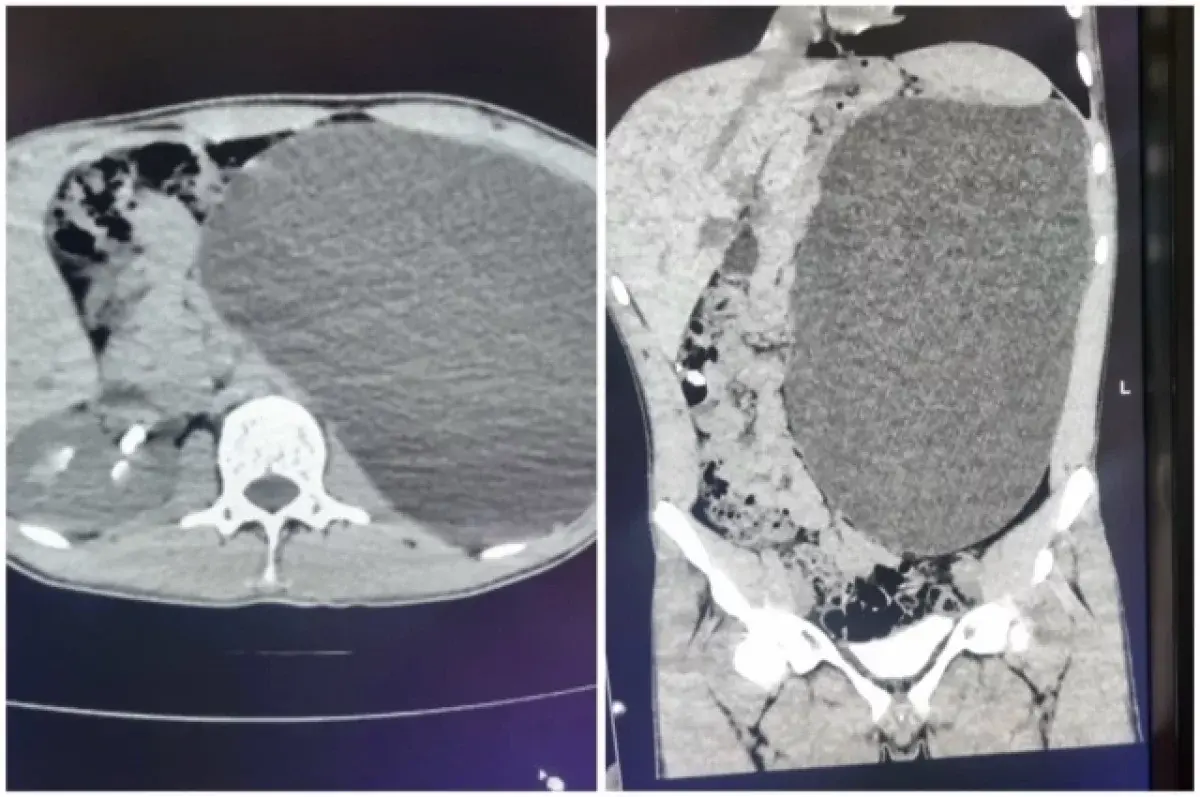

В Новосибирске подростку удалили почку размером с пятилитровую бутылку

Фото: Сиб.фм / Министерство здравоохранения Новосибирской области

В Новосибирске подростку 17 лет удалили воспалённую почку, которая увеличилась до размеров пятилитровой бутылки. Об этом пишет «АиФ-Новосибирск».

Детский хирург-уролог Ирина Живолуп диагностировала гидронефроз — расширение полостной системы почки из-за нарушенного оттока мочи. Болезнь протекала бессимптомно, но могла привести к серьёзным осложнениям, включая разрыв почки и внутрибрюшное кровотечение.

Операция прошла через небольшие проколы: орган и скопившуюся жидкость удалили, предотвратив опасные последствия. Несмотря на тяжесть ситуации, родители дали согласие на вмешательство после разъяснений врачей. Сейчас Михаил восстанавливается и вскоре сможет вернуться к обычной жизни. Медики отмечают, что жизнь с одной почкой возможна, так как второй орган полностью берёт на себя функции.